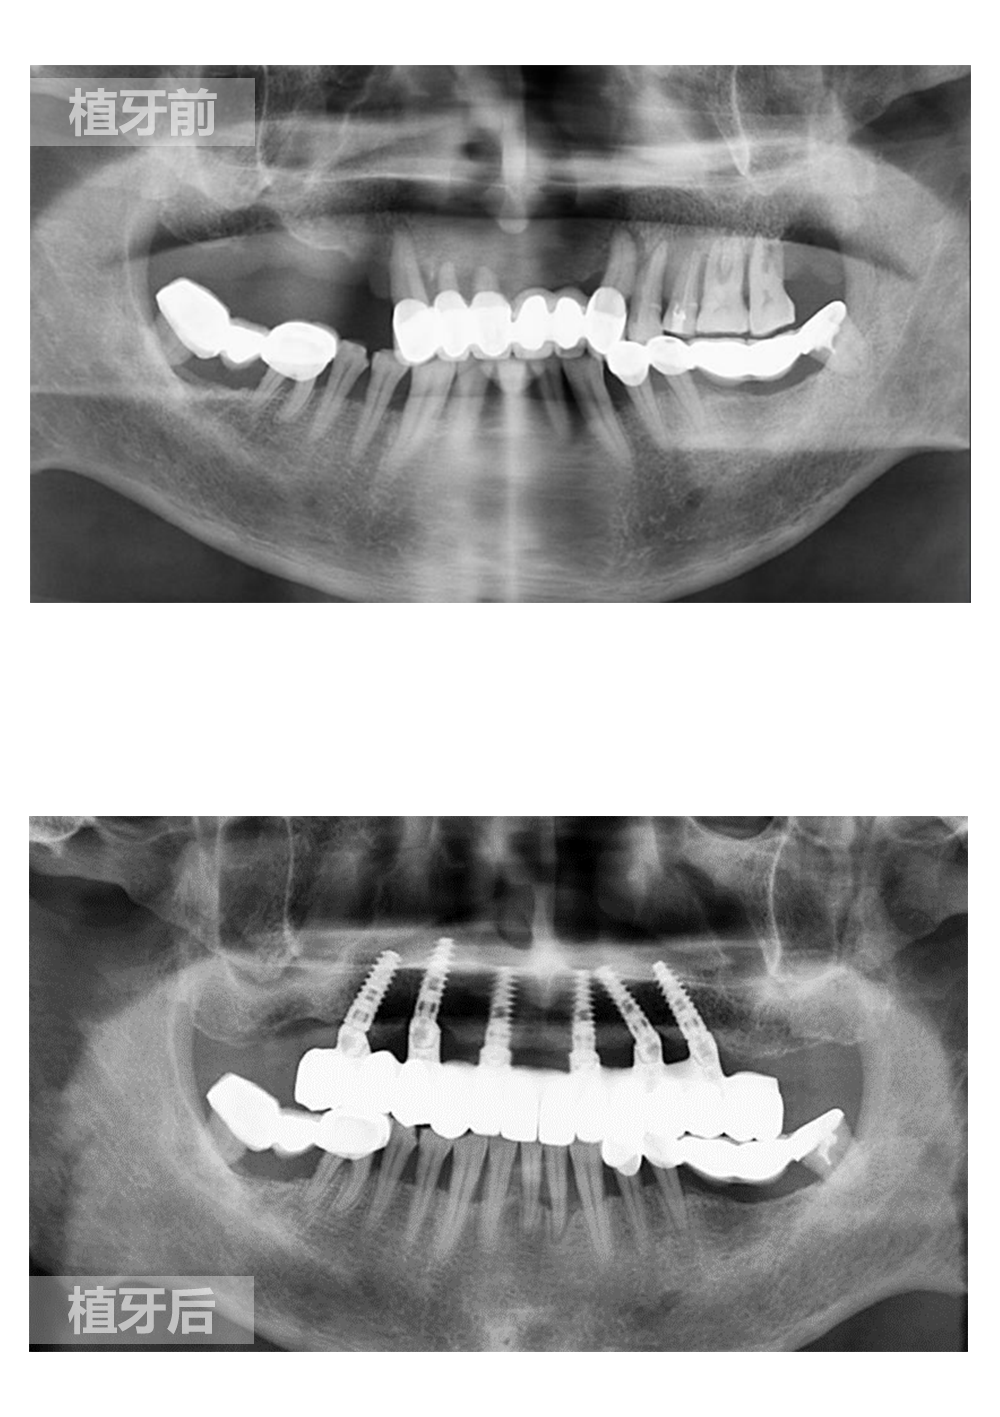

种植牙是在牙骨内植入人造牙根(即种植体),用来支持人造牙冠(义齿)。

种植牙要能够稳固地固定在颌骨内并将支持人造牙冠(义齿)。种植体是使用钛金属、钛合金或陶瓷制作的小螺钉 – 这些材料都具有很好的生物相容性,被人体接受。同时,钛金属与人类骨骼之间的结合效果十分优异。

局部麻醉状态下,进行种植体植入手术。种植体与骨牢固结合愈合后,人工牙根将为上部裸露牙冠提供支撑。